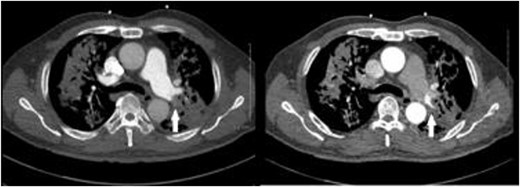

A 57-year-old male presented to the Emergency Department unwell with central chest pain, dyspnoea, and haemoptysis. CT pulmonary angiogram demonstrated bilateral cavitating pneumonia. Irregular nonenhancement of a segmental pulmonary artery in the left upper lobe was also noted (Fig. 1). CT thorax in systemic arterial phase demonstrated enhancement of this segmental branch in the left upper lobe (Fig. 1). These findings are due to reversal of flow in the pulmonary artery branch due to higher pressure blood from the bronchial artery passing through the fistula. The patient was brought to interventional radiology for further investigation and management. An initial nonselective descending aorta angiogram demonstrated the bronchial artery-pulmonary artery fistula in the left upper lobe. Selective cannulation of the enlarged left bronchial artery was then performed followed by microcatheter cannulation of the main feeding vessels to the fistula. The vessels were embolized to stasis with 400-μm microparticles (Embozene 400) and microcoils (Fig. 2). The patient tolerated the procedure well and had an uncomplicated postprocedural course. Pansensitive tuberculosis detected on sputum sample. Treatment with Rifater, pyridoxine, and ethambutol were commenced. No further episodes of haemoptysis have been noted to date on clinical follow-up.

CT pulmonary angiogram (left) demonstrates non-opacifying segmental pulmonary artery (white arrow); on the CT systemic arterial phase angiogram (right), the same segmental pulmonary artery opacifies; background cavitating consolidation is seen in both lungs.